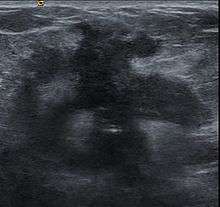

Clinical presentation of a lump in the breast is histologically viewed as a collagenous tumor or desmoplastic response created by myofibroblasts of the tumor stroma.[18] Proposed mechanisms of activation of myofibroblasts are by immune cytokine signaling, microvascular injury, or paracrine signaling by tumor cells.[18]